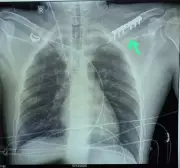

Doctors at NRS Hospital in Kolkata performed a bronchoscopy to extract a 2 cm seed from a 13-year-old girl's airway, restoring her breathing after severe symptoms.

An 11-year-old boy from Dahod was saved after ENT specialists at SSG Hospital performed emergency bronchoscopy to remove a pin lodged in his right main bronchus, preventing a fatal outcome.